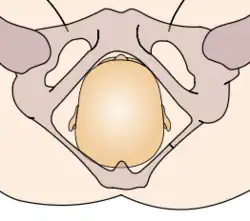

Durante la mecánica del parto, los diámetros menores del feto pasan por los diámetros mayores de la pelvis materna. Con el fin de no quedar encajado en algún punto durante su trayectoria fuera del útero, el neonato pasa por una serie de movimientos naturales que constituyen el mecanismo del parto.

- Extensión: la cabeza del feto atraviesa el canal del parto, se extiende de tal manera que la frente se desplaza primero por el orificio vulvar. La cabeza está por debajo de la sínfisis púbica y ha distendido al máximo el perineo.

- Rotación externa: una vez que ha salido la cabeza, se gira 45° para restaurar su posición original antes de la rotación interna y quedar en posición normal en relación con los hombros. Se denomina por ella la restitución, haciendo el paso de los hombros más factible.

Estos movimientos son todos debido a la relación que existe entre la cabeza ósea y hombros del feto y el anillo óseo de la pelvis materna.